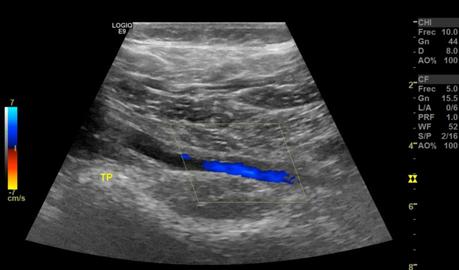

Las venas tibiales anterior, posterior y peroneas sin evidencia de alteraciones, con adecuado llenado de señal color, sin alteraciones a las maniobras de esfuerzo, con adecuada respuesta a la maniobra de aumento.